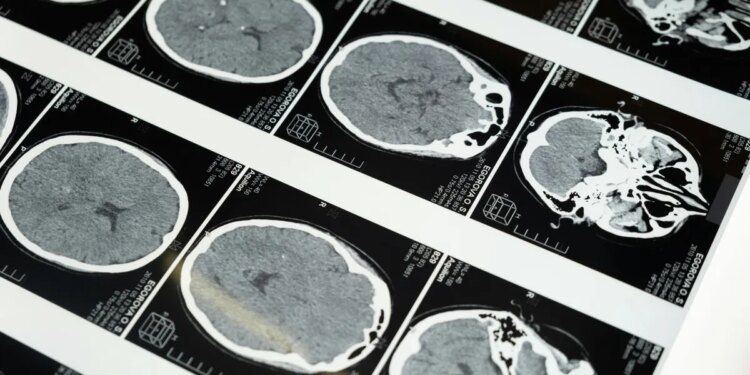

Brain imaging highlights the regions researchers study as companies explore noninvasive ultrasound brain-computer interface technology. (Kurt “CyberGuy” Knutsson)